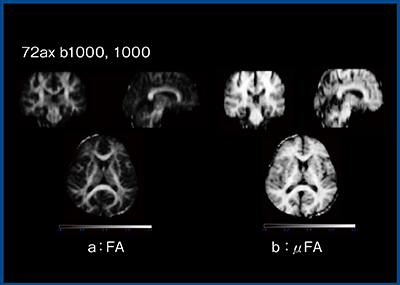

近年,海外においてはMPGの印加方法が議論されている。通常,DTIでは1回の撮像中に1方向に1回だけMPGを印加するが,これを複数方向に複数回印加する方法がDDEである。DDEでは,MPGの向きや大きさ,MPG間の時間も調整可能であり,μFAなど,さまざまな応用が報告されている。今回,ZGOに研究用シーケンスとしてリリースされ,例えばMPGを2回印加した場合の2回目の印加方向を変化させ,その信号変化からボクセル内を構成する要素の異方性をマップ化するμFAマップが作成可能となり2)(図7),今後はさまざまな検討を行っていけると考えている。

図7 ZGOによるDDEのμFAマップ